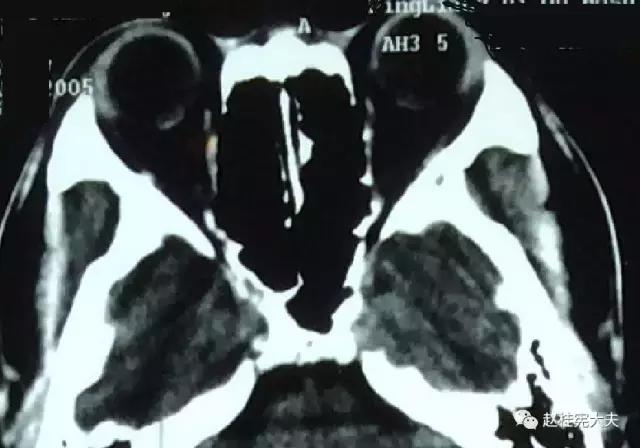

我们先以两张图片看看CT和磁共振分别能看到什么?

CT

眼眶黑乎乎一片,细致结构无法清晰显示